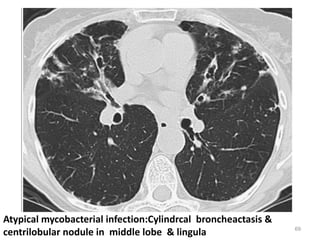

Atypical mycobacterial infection:Cylindrcal broncheactasis &

centrilobular nodule in middle lobe & lingula